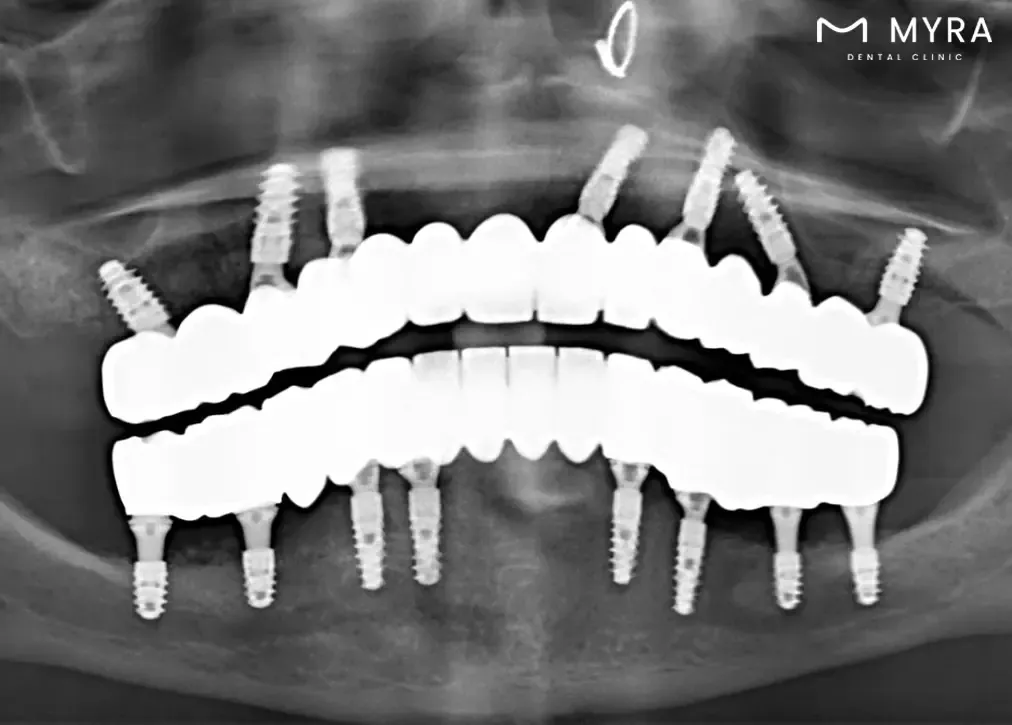

Implant Surgery Planning: Sirona 3D Dental Tomography is utilised to assess the bone structures of the jaw, allowing for precise planning of implant surgeries. The detailed images aid in determining the optimal placement of dental implants.

Detailed Imaging for Treatment Stages: The technology is frequently used in various treatment stages, including planning for implant surgery by advanced procedures, root canal treatment, and orthodontic interventions. The detailed imaging allows for precise assessments, contributing to successful outcomes in these procedures.

Efficient Planning for Implant Surgery: The technology is particularly useful in planning and guiding implant surgeries. It allows for a thorough evaluation of the jawbone structure, facilitating precise implant placement and increasing the likelihood of successful outcomes.

Sirona 3D Dental Tomography allows dentists to gain a more in-depth understanding of dental and jaw-related issues. The three-dimensional images enable precise and accurate diagnoses of conditions such as tooth decay, buried or impacted teeth, fractures resulting from trauma, bone defects, and the periodic assessment of implants.

The procedure aids in treatment planning by offering a higher level of detail and accuracy. Dentists configure root canals, measure root canal dimensions, and conduct detailed assessments of bone density, sinuses, and joints. The technology helps in the planning of dental implant procedures, offering a three-dimensional evaluation of the jawbone structure.

Imaging before Implant treatment is very important. Because the 3D tomography X ray shows the condition of the jawbone very clearly, they contribute to proper planning before surgery. Bone density is a measure of bone density. Thus, it is determined which surgical techniques will be used and exactly what can be done before the procedure begins. After surgery, CT scans can be taken to control implant placement and bone support.